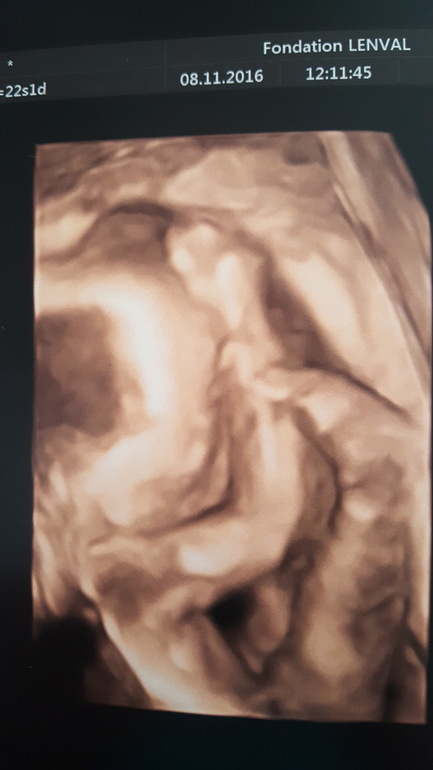

Вчера 08/11/2016 ездили с мужем на УЗИ. Со здоровьем у малыша все хорошо, как и первый, будет крупный, так как все параметры по верхней границе. Надеюсь, что рожу раньше ПДР недели на 2-3😊

Всё время малыш спал и никак не реагировал на попытки узистки его разбудить. Личико прикрывал ручками и ножкой. Причем на фото правая ручка и левая ножка. Непонятно как можно уснуть в таком положении:)